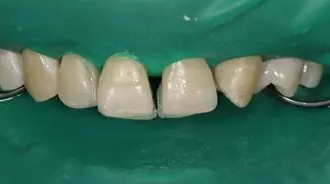

8.分層堆塑:硅橡膠背板就位于口內(nèi),使用瓷納美E2 色樹脂進(jìn)行腭側(cè)堆塑,形成厚約為 0.5mm 腭側(cè)釉質(zhì)壁,光照20s,移走硅橡膠背板,腭側(cè)繼續(xù)光照 20s。接著使用 D2 色樹脂進(jìn)行充填,注意充填的厚度約為0.5mm,長度短于切端1~2mm,且頸部的厚度應(yīng)逐步遞減。然后使用 E2色樹脂恢復(fù)唇面及切端,厚度約為1~1.5mm。堆塑時(shí)應(yīng)兩顆牙同時(shí)進(jìn)行,以便及時(shí)調(diào)整牙齒的寬度,堆塑完成后應(yīng)檢查兩牙寬度是否一致,是否協(xié)調(diào)對稱,有無懸突等。

病例分享|復(fù)合樹脂微創(chuàng)美學(xué)修復(fù)關(guān)閉上前牙間隙

E2樹脂堆塑腭側(cè)釉質(zhì)壁

移除硅橡膠導(dǎo)板后

D1 色,E2色分層堆塑完成